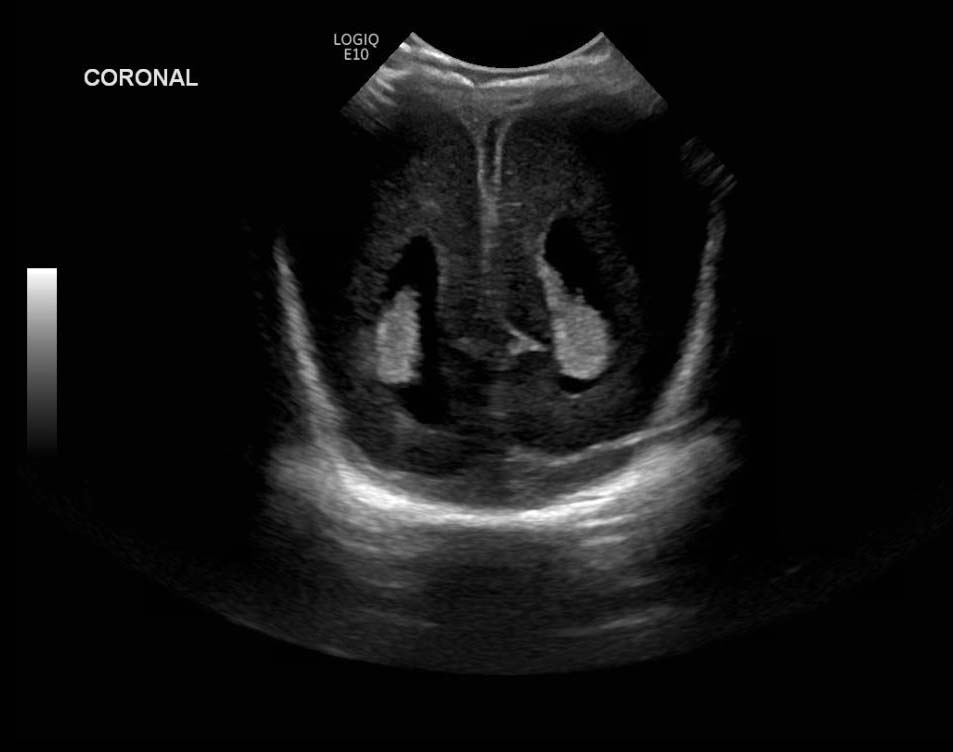

Age: 4 days (born at 24 weeks)

Sex: Male

Indication: Evaluate for germinal matrix hemorrhage

Grade 2 germinal matrix hemorrhage

Sample ReportLeft germinal matrix hemorrhage involving the caudothalamic groove and layering in the occipital horn of the left lateral ventricle without hydrocephalus (grade 2).

No abnormal brain parenchymal echogenicity or extra-axial collections.

Premature sulcation pattern.